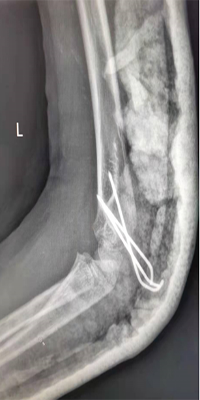

肱骨髁上骨折闭合复位交叉克氏针内固定术